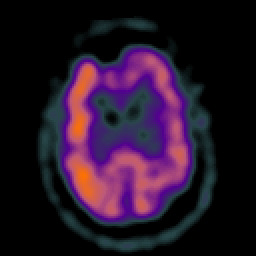

Subacute Stroke overlay -- Slice #16

[Home][Help][Clinical] Slice 16